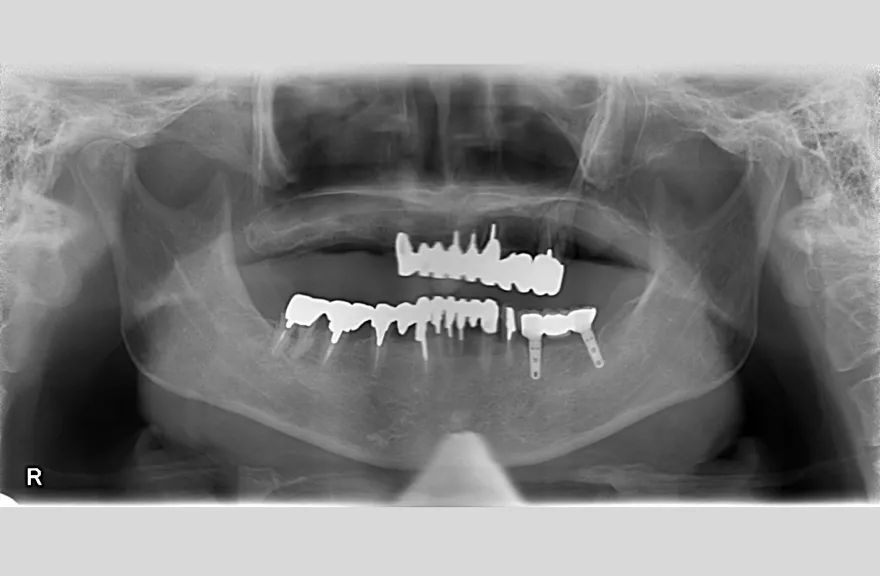

骨格の前後的な差がある方でした。術前のレントゲンより、上下で歯牙の損傷に明らかな差があるのがみてとれます。

既にインプラント治療がなされており、使えるインプラントを使いながら足りないところにインプラントフィクスチャーを埋入し、噛み合わせを再構築する必要がある方でした。

上の前歯、右上の奥歯のインプラントはもう既に使える状態ではなく、また年月を経てすり減ってしまった下の前歯は噛み合わせを再構築する上で利用が難しい状況でした。

レントゲンをよく見るとお分かりいただけるかと思いますが右下の奥歯のインプラント(レントゲンでは左右逆にうつるので、左下)が既にインプラント周囲炎になっていました。

本当に治療をやり切ってしまうなら、右下の奥2本のインプラントを抜去、新しいインプラントフィクスチャーを埋入すべき症例でした。

しかし、患者さんとの話し合いで、「まだ使えるインプラントは置いておこう」ということになり、右下のインプラントは置いたまま治療を行っています。今後の人生の中で腫れたり痛む可能性があることは重々ご承知いただいております。

複数のインプラントフィクスチャーの埋入においては埋入位置がずれると後々のクラウン製作に難が生じます。そのリスクを最低限にするため、ガイデッドサージェリーを行っております。